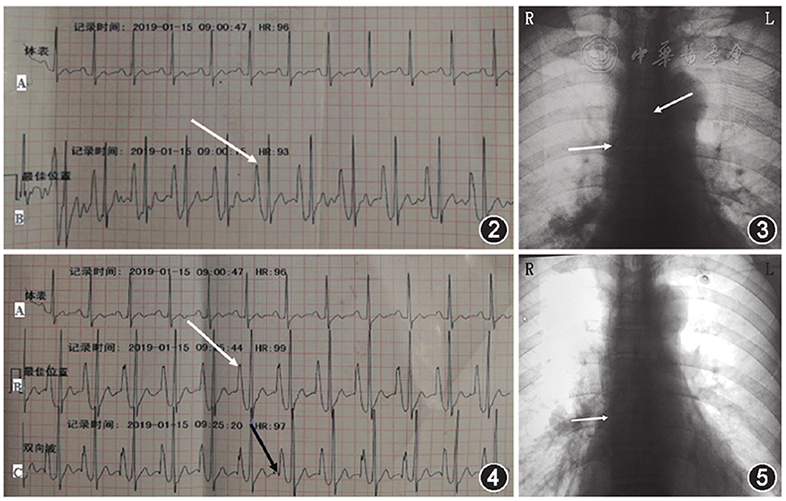

患者,男性,55岁,肺腺癌(T3N3M0期,Ⅲc期),因治疗需要行PICC置管。患者有PICC置入史及化疗史。采用血管超声横向及纵向评估上臂贵要静脉、肱静脉、腋静脉及锁骨下静脉,检查血管直径、是否有狭窄畸形变异等现象。根据导管和静脉管径的比值≤45%原则选择血管[4],选择贵要静脉为目标血管,直径0.5 cm,评估穿刺部位皮肤完整性,进针穿刺部位选取上臂中段区域。患者在超声联合改良赛丁格技术下经左上臂贵要静脉行Power PICC植入术,血管穿刺及导丝送入血管过程顺利,利用体表骨性标志预测置管长度为46.5 cm,送管前根据预测长度修剪PICC导管,送管过程顺利,未发生送管困难,一次送管成功。采用血管超声检查锁骨下静脉,导管在位,通过超声联合注射器推注生理盐水试验,观察颈内静脉无白色亮点及雪花状喷洒现象,初步排除导管异位。术后CXR显示导管末段在SVC内打折成8字型,导管尖端位于气管隆突上方约1 cm处,导管反折长度约2.5 cm(图1)。

患者返回血管通道中心,重新对穿刺部位导管和皮肤进行消毒,根据胸部X线片上电子标尺测量导管打折长度约2.5 cm,故将导管从静脉中拔出3 cm,然后重新送入导管。连接科曼C100心电定位仪,4个电极片分别贴于右锁骨下(RA)、左锁骨下(LA)、左下(LL)腹部、右下(RL)腹部,屏幕抓取二导联心电波形原始资料记录患者基础心电图,取下RA导联,将无菌导联线鳄鱼夹一端夹在20 ml注射器注射针头针柄上,一端连接心电定位仪,采用生理盐水引导腔内心电图定位方法,心电图显示P波高尖,P波振幅等于QRS波振幅的1/2(图2),提示导管尖端位于SVC中、下三分之一。随后拍摄的CXR显示导管尖端位于SVC中段,导管末端仍然反折成L型(图3)。故进行第二次导管尖端位置调整,在心电图定位下,拔出部分导管,直到高P波消失。然后轻柔缓慢将导管再次送入血管至导管0刻度位置,观察P波振幅从正常到高尖,但未观察到负向P波改变,继续将导管0刻度后1 cm长度导管送入血管,观察到高尖P波前有一个负向小P波,即双向P波(图4)。最后,将导管拔出1 cm,导管外露0刻度。再次拍摄的CXR显示导管尖端位于SVC的下三分之一处(图5)。